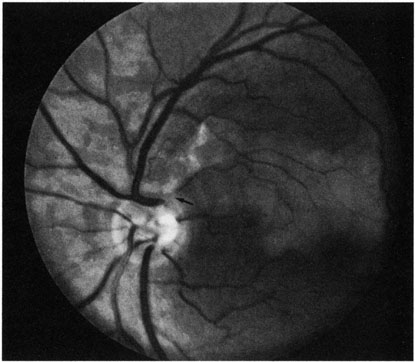

Obstruction of one of the posterior ciliary arteries may result in a whitening of the area of the retina supplied by the involved posterior ciliary artery and the subsequent appearance of patchy pigmentation in the same area. However, in patients with anterior ischemic optic neuropathy secondary to temporal arteritis the retina may appear normal (Fig. 5). In the case of either the medial posterior ciliary artery or the lateral posterior ciliary artery, the area involved is the size of approximately half of the choroid.121–123 In the case of a long posterior ciliary artery, the temporal side of the eye including the macula is involved.121

Fig. 5. A: Ischemic optic neuropathy in a patient with giant cell arteritis. B and C: Intravenous fluorescein angiography demonstrates delayed filling of the lateral posterior ciliary artery.

We have seen several patients with anterior ischemic optic neuropathy with suspected temporal arteritis where the Westergren sedimentation rate and C-reactive protein were normal and the intravenous fluorescein angiogram helped confirm the diagnosis (Fig. 5).